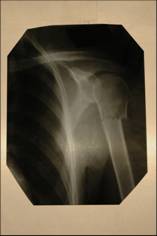

Андрей

После лечения:

Андрей после лечения

До лечения:

Андрей до лечения